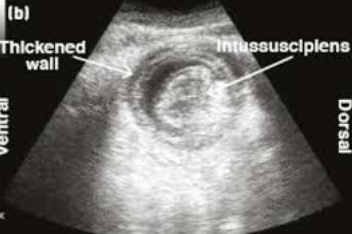

what is intussusception?

telescoping of the intestine: one segment (intussusceptum) passes inside an adjacent segment (intussuscipiens)

causes venous occlusion (edema, engorgement, and thickening)

how is intussusception diagnosed?

3. US: SI distention and target lesion